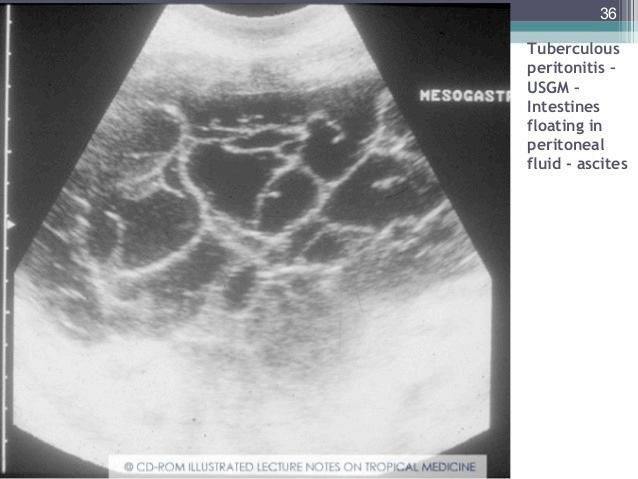

C.8 TB Gastrointestinal

Pasien dengan TB peritoneum biasanya bermanifestasi sebagai TB gastrointestinal, ditemukan pada individu berusia <40 tahun dan frekuensinya lebih besar pada perempuan. Manifestasi klinisnya tidak spesifik dan mirip dengan penyakit gastrointestinal lainnya.

: Peritonitis Tuberkulosis

Perikarditis TB dapat terjadi melalui ekstensi dari kelenjar limfe mediastinum atau fokus paru subpleura, menghasilkan efusi perikard, perikarditis konstriktif, atau tamponade.

Patogenesis inflamasi yang berat menjadi dasar pertimbangan kortikosteroid adjuvan pada kondisi terpilih sesuai pedoman.